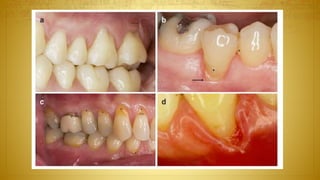

Free connective tissue graft combined with a

coronally advanced fl ap procedure – single

recession

(a) Deep gingival recession at a cuspid with

minimal height of keratinized tissue apical

to the root exposure.

(b) The graft has been sutured to leave an area

between the cemento-enamel junction and the

graft available for the marginal keratinized

tissue of the flap.

(c) The flap has been advanced coronally and

sutured.

(d) Clinical healing at 1 year.